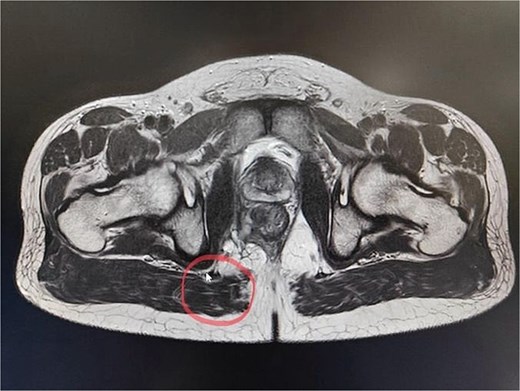

CT scan of the pelvis suggested a chronic inflammatory process. An MRI Perianal Region/Fistulogram (Fig. 1) was done and the findings were as follows: A possible fistulous tract was observed in the right perianal region, with a distal blind end in the intergluteal cleft. The presence of a fistulous tract and its extent was unclear. MRI findings could not differentiate between infectious, inflammatory, or neoplastic processes but it can definitely point out the presence of an abscess, which was not the case in our patient. Owing to the difficulty in establishing the diagnosis a colonoscopy was done and the findings (Figs 2 and 3) were as follows: A semicircumferential area from 7 to 11 o’clock position with tiny erosions was noted, which extended 4 cm from the anal verge.

A possible fistulous tract was observed in the right perianal region, with a distal blind end in the intergluteal cleft. The fistulous tract does not involve the anal sphincter complex/levator ani muscle.